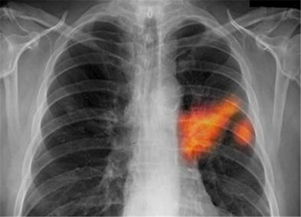

胸部X線檢查一般拍攝正位像和側(cè)位像,根據(jù)需要再進(jìn)行斷層攝影。 腺癌占肺野型肺癌的絕大部分,一般陰影較淡,大多數(shù)情況下,用普通攝影識別困難。如果是??漆t(yī)生,可以比較容易地發(fā)現(xiàn)不滿2厘米的早期癌。 鱗癌占肺門型肺癌的絕大部分,因病灶被心臟和大血管等所掩蓋,早期的X線照片上的特點(diǎn)是,未顯示出異常。但如果瘤體再增大,可發(fā)現(xiàn)阻塞性肺炎、肺不張等間接的異常。??漆t(yī)生可根據(jù)見到的支氣管變狹窄和阻塞的狀態(tài),來間接判斷癌的存在。一般來說,開始能看到癌的陰影時(shí),瘤體已經(jīng)很大了。來自合肥鳳凰腫瘤醫(yī)院專家回答

X線檢查通過X線檢查可以了解肺癌的部位和大小,可能看到由于支氣管阻塞引起的局部肺氣腫、肺不張或病灶鄰近部位的浸潤性病變或肺部炎變。2。

這些檢驗(yàn)有助于診斷疾病、計(jì)劃和指導(dǎo)治療、或監(jiān)測疾病的進(jìn)展。3. 胸部 x 片:x 射線可觀察到胸腔內(nèi)器官和骨骼的情況。

x 射線是一種能穿透人體的光束能源,可顯影人體內(nèi)部臟器的情況。4. 胸部 X 線通常用于拍攝胸腔內(nèi)的臟器和骨骼,X 線穿透人體并顯影到膠片上5. CT(CAT)掃描:此檢查可從不同的視角掃描、拍攝體內(nèi)的不同區(qū)域從而獲得該區(qū)域一系列的詳細(xì)圖片,如胸部。